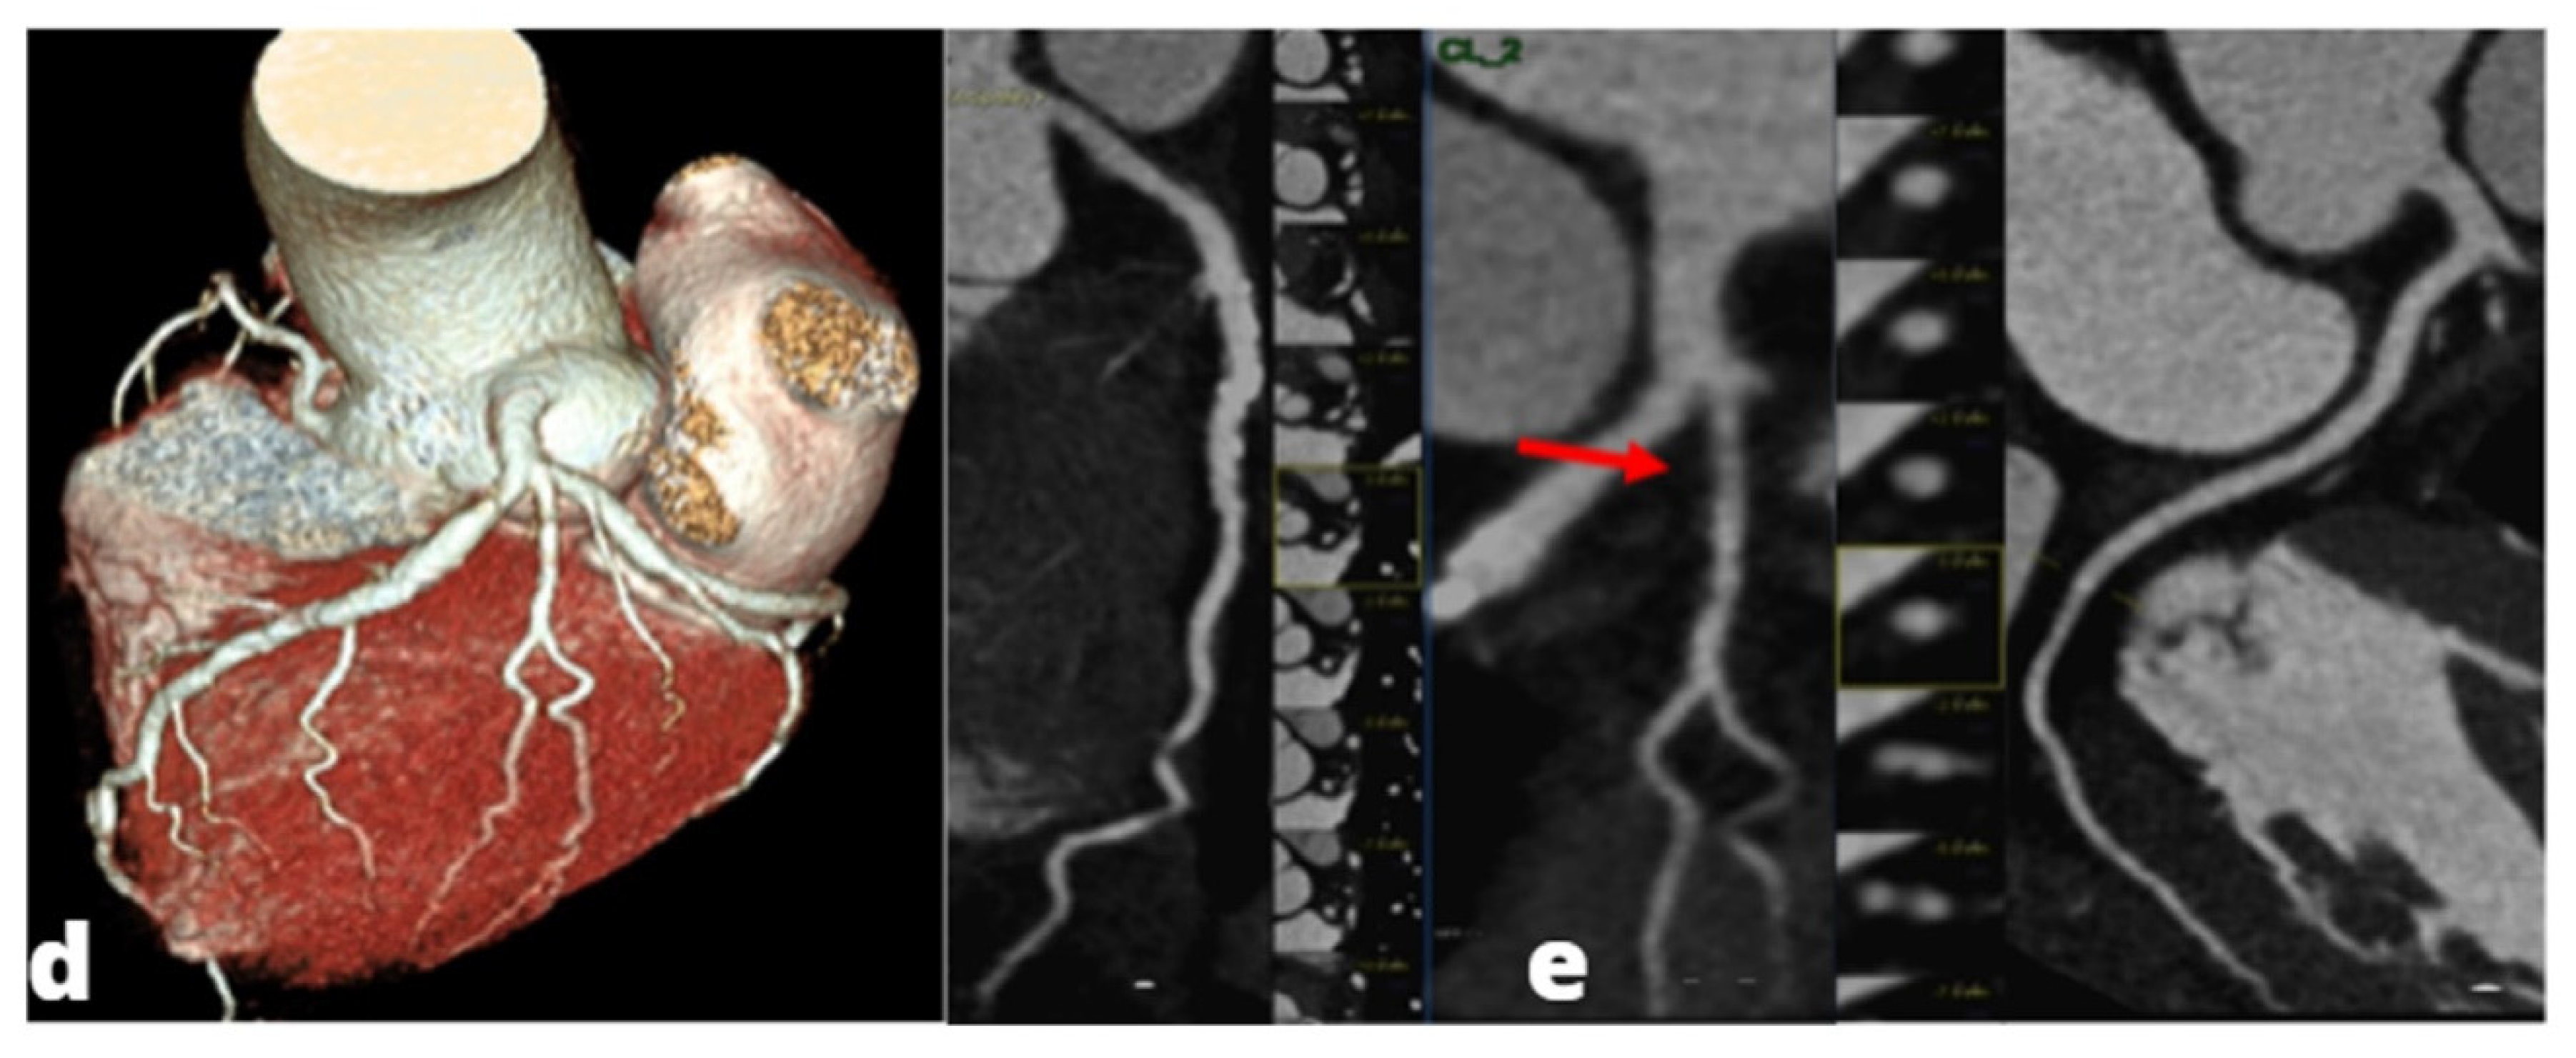

Figure 1. A young adult presenting at emergency department with acute chest pain, subtle ST alterations in the lateral wall of the left ventricle and cardiac enzymes elevation. Cardiac MRI was performed 48 h later demonstrating edema in the inferior-lateral wall of the left ventricle (a) associated with hyperemia in early gadolinium enhancement (b) and post-inflammatory fibrosis using late gadolinium enhancement sequences (c).